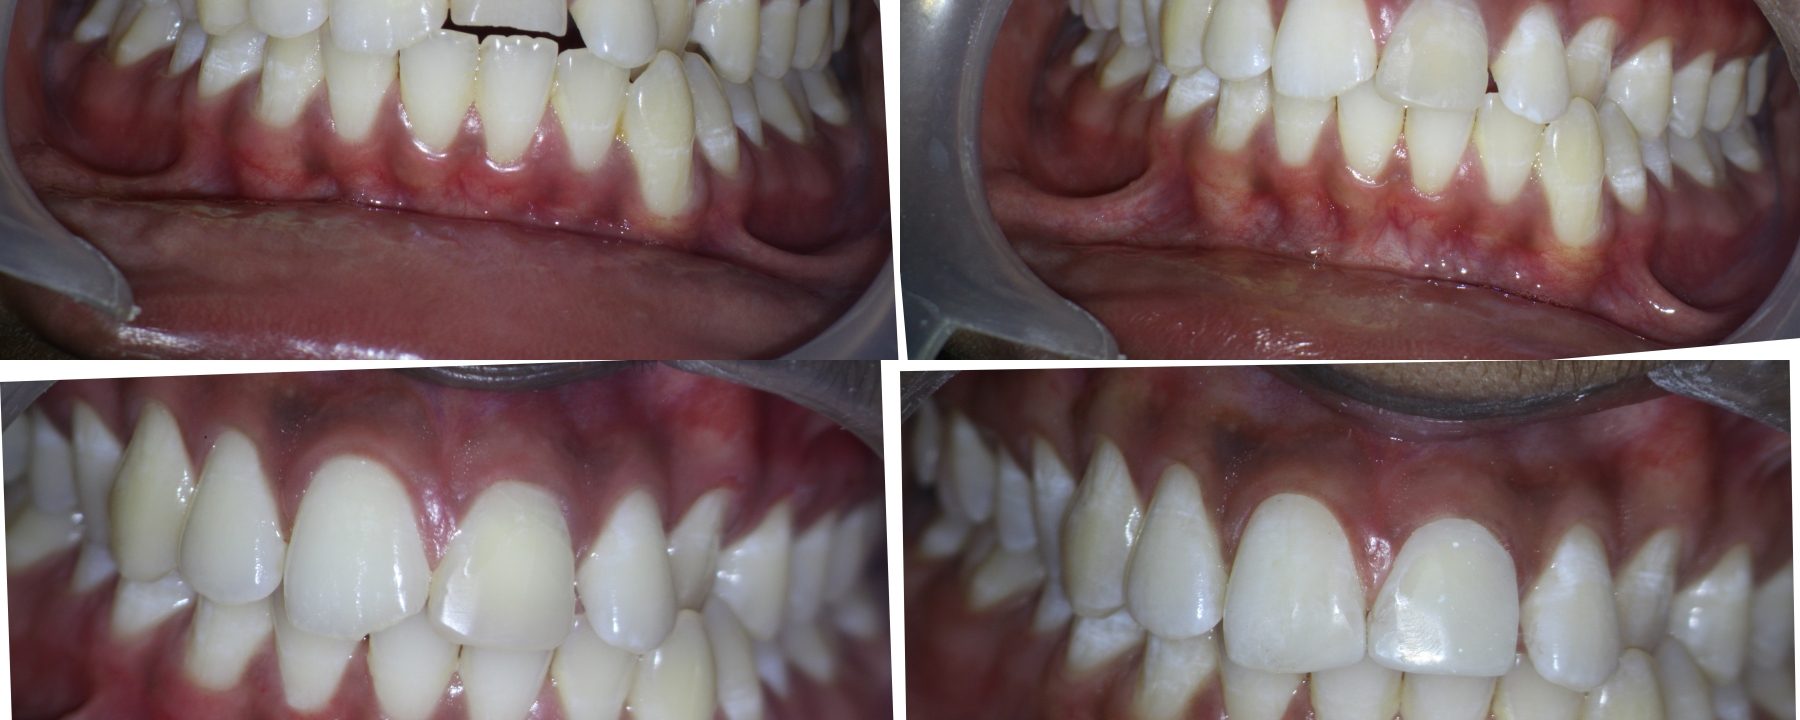

Crown fracture extending sub-gingival

Pt 55 yoM presented with fracture of #9.  History of trauma 2 wks back and was aymptomatic. Gingivectomy using electrocautery was done. Root canal therapy was completed after intermittent CAOH dressing , fibre post cemented and composite build up was done.